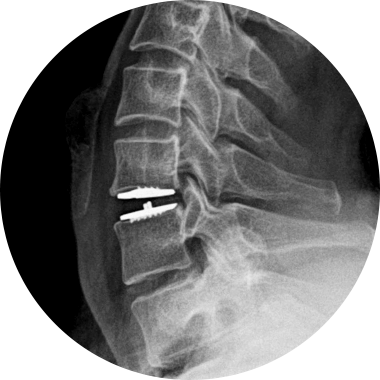

손상된 경추 디스크를 제거한 후, 척추체 사이에 인공디스크를 삽입하는 수술적 치료입니다.

손상된 경추 디스크를 모두 제거하고 빈 공간으로 인공디스크를 삽입하여 본래의 디스크처럼 정상적인 기능을 하도록 합니다.

STEP 01

손상된 디스크

STEP 02

손상된 디스크 제거

STEP 03

인공디스크 삽입